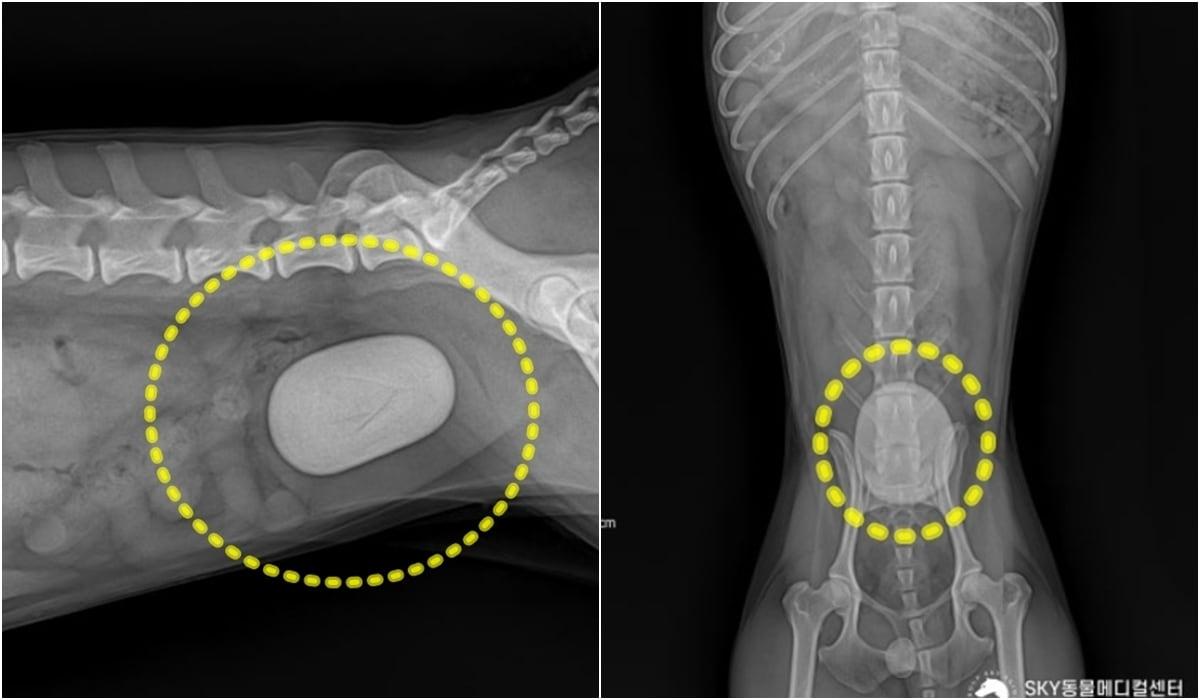

본문 이미지 - 혈뇨 증상으로 동물병원에 내원한 푸들의 방사선 검사에서 발견된 거대 결석(광주 스카이동물메디컬센터 제공) ⓒ 뉴스1

혈뇨 증상으로 동물병원에 내원한 푸들의 방사선 검사에서 발견된 거대 결석(광주 스카이동물메디컬센터 제공) ⓒ 뉴스1